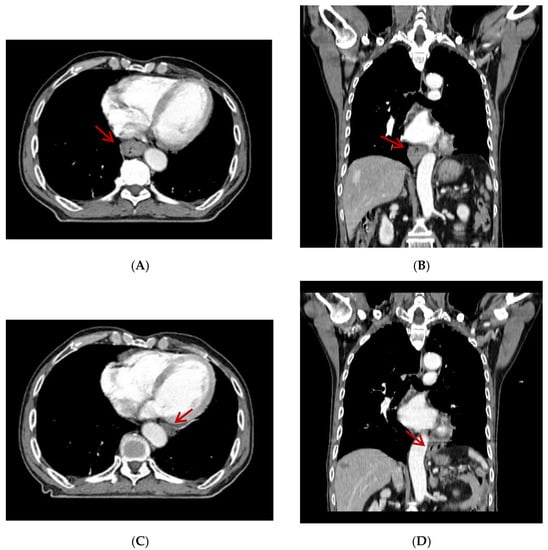

A 79-year-old man was diagnosed with esophageal cancer during an evaluation of dysphagia. Upper endoscopy revealed a lumen-encircling mass 32 cm from the incisors (Figure 1); a biopsy specimen revealed squamous cell carcinoma. Distal esophageal wall thickening and multiple metastatic lymph nodes were observed upon computed tomography (CT) of the chest and abdomen (Figure 2A,B). The esophageal cancer stage was T4N2M0.

Figure 1. Endoscopic finding of the esophageal lesion.